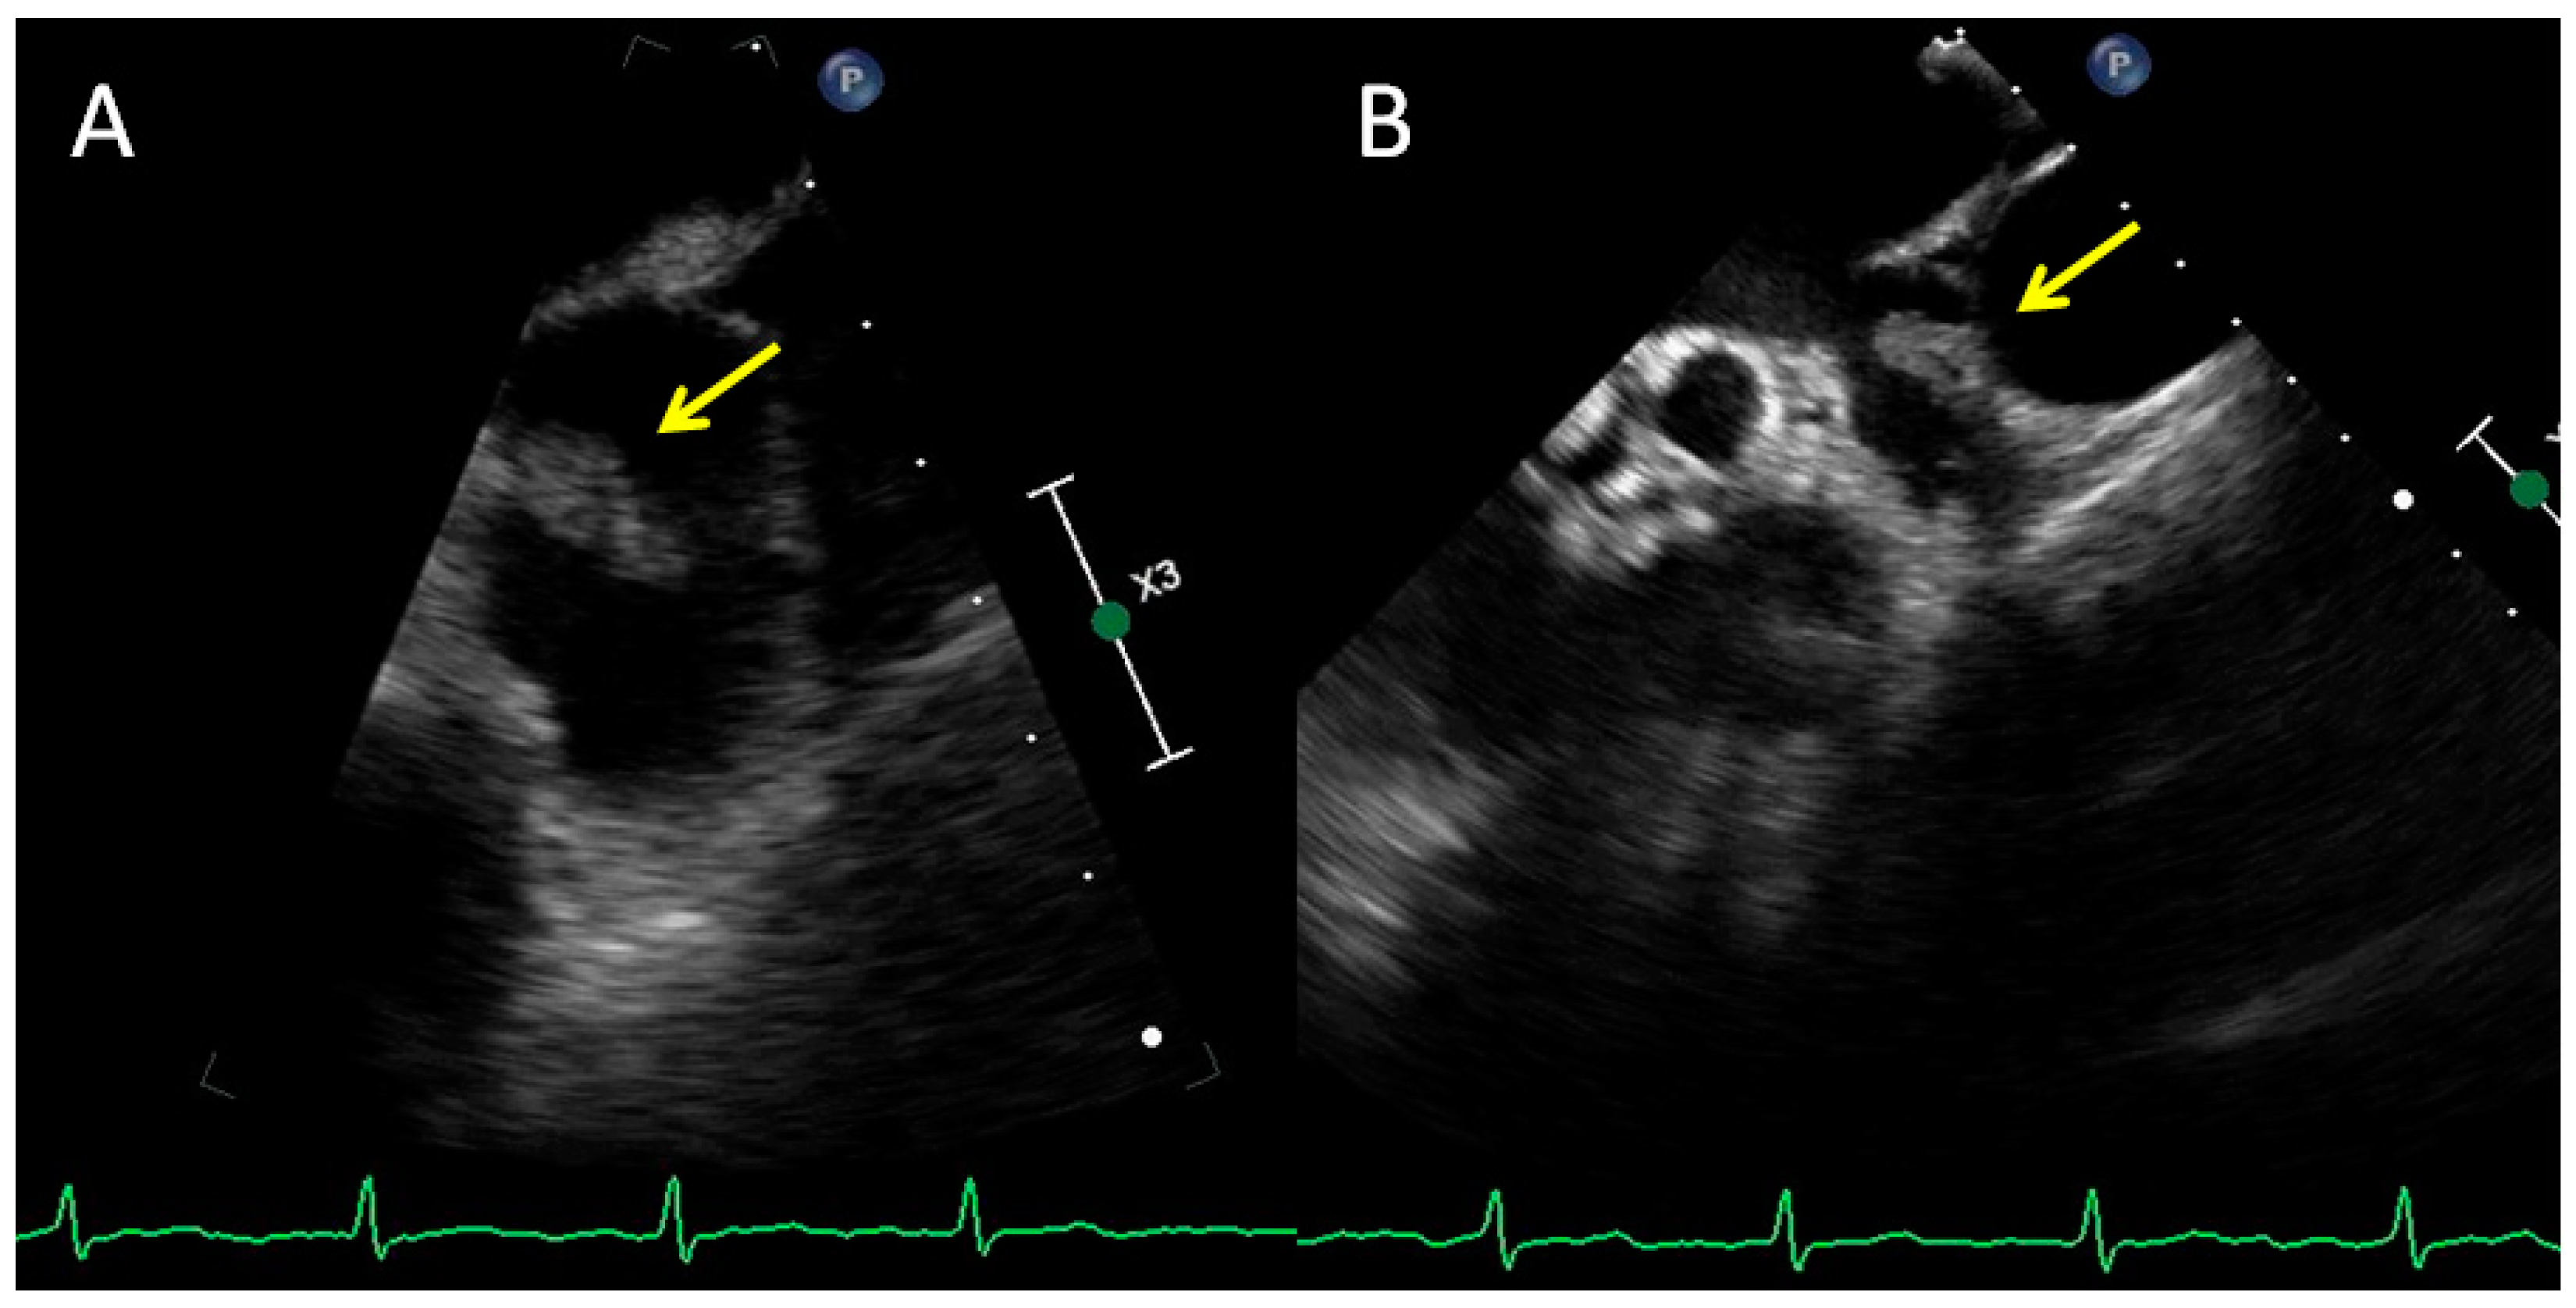

Echocardiography, Computed Tomography and Magnetic Resonance Imaging in the Differential Diagnosis of a Tumor in the Left Atrium of the Heart